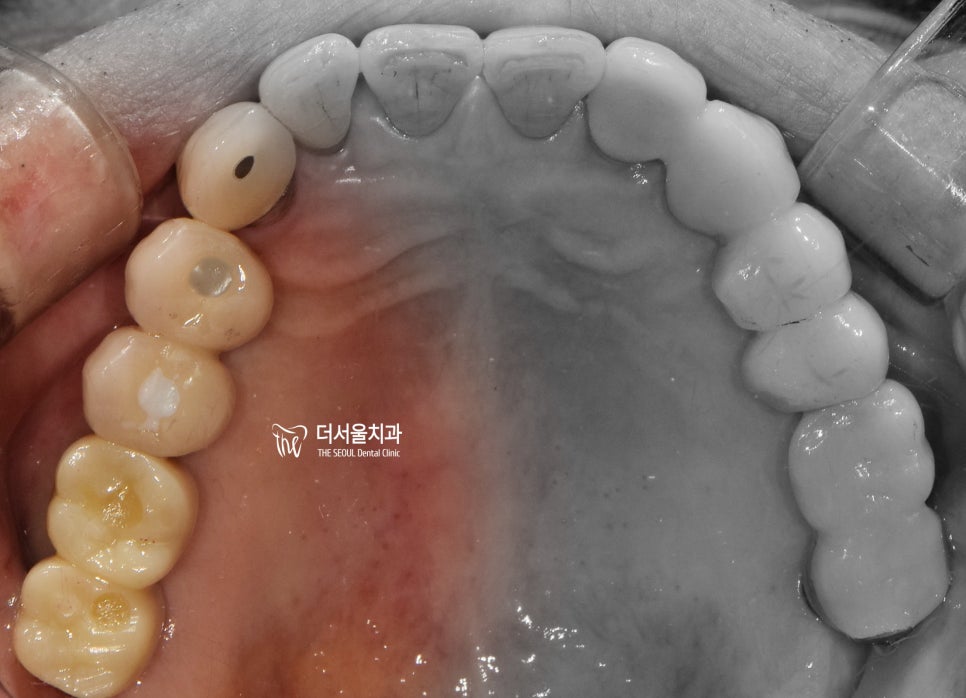

본론에 들어가기 전에 먼저

구강 내 사진도 보여드리겠습니다.

정면에서 봤을 때는 구강 내 전체적으로,

치은 퇴축이 심하다는 것을 볼 수 있습니다.

블랙트라이앵글 형성 및

잇몸이 아래로 내려감에 따라서

치아의 치경부(cervical)쪽이

다 드러나 있는 상황이네요.

교합면에서는 크게 잘못 된 느낌을

받을 수 없죠?

하지만, 그 아래에서는 이미

염증 및 골 소실에 따라서 치아들이

생활력을 잃어가고 있는 중이였습니다.

그래서 사진에서 보시는 것 처럼,

4개월 가량을 기다려서 뼈와 잘 아문것을

확인했고 이어서 지르코니아 크라운 및

PFM 크라운을 연결해드렸습니다.

앞쪽에 있는 2개의 크라운은 PFM 이며,

뒤에 있는 2개는 지르코니아 크라운입니다.

차이가 좀 많이 나죠?